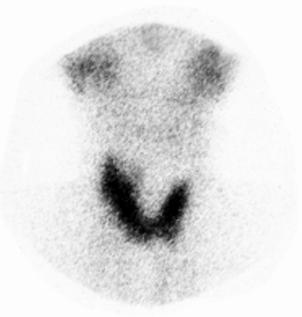

Figura 5. Cintilograma tiroideo en la fase de recuperación de la tiroiditis subaguda.

Mismo caso de la figura anterior, 1 1/2 mes después del primer estudio y luego de tratamiento con prednisona, el cintilograma tiroideo muestra una tiroides normal (captación tiroidea de I-131/24h 20 %).